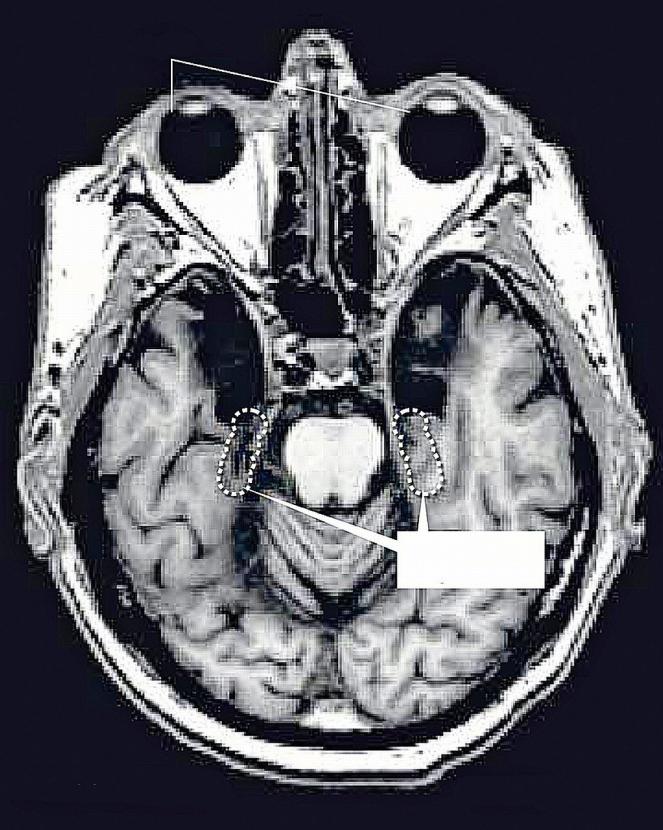

Po amputacji hipokampów objawy padaczki były mniej dotkliwe, pacjent utracił jednak zdolność posługiwania się pamięcią.materiały prasowe Po amputacji hipokampów objawy padaczki były mniej dotkliwe, pacjent utracił jednak zdolność posługiwania się pamięcią.